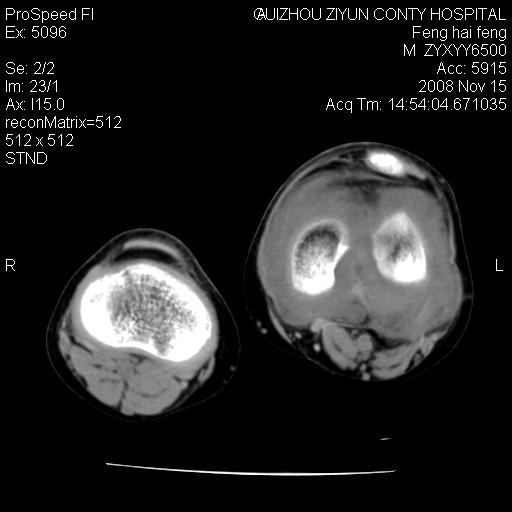

标题: CT16656:M 14Y 左膝关节肿胀一年余。其余病史不详。 [打印本页]

标题: CT16656:M 14Y 左膝关节肿胀一年余。其余病史不详。

考虑左侧髌骨结核;左膝关节滑膜肿胀、增厚,关节囊积液。

左膝滑膜型关节结核可能性大!支持!滑膜型关节结核主要ct表现:关节囊肿胀,积液,关节面见小破坏灶,并见点状死骨!

好大的左腿!考虑左侧髌骨结核,左膝关节滑膜肿胀、增厚,关节囊积液。

左侧髌骨结核;左膝关节滑膜肿胀、增厚,关节囊积液